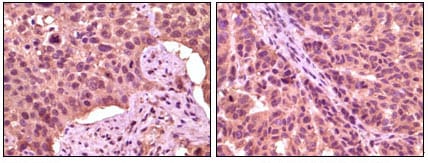

分类: 科研抗体货号: 20084别名: SR; BCSG1应用: IHC反应种属: Human

分类: 科研抗体货号: 20089别名: DKFZp686D0638; GSK3A应用: IHC反应种属: Human